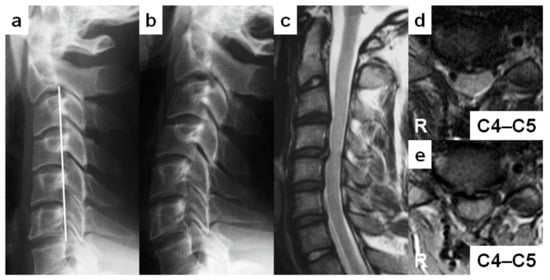

| 3 | 24 | Man | 0.1 | − | Pastry chef | Traffic accident | C4–C5 | 16 | + | 17 |

| 3 | Reverse sigmoid | + | C3, C4, C5, C6, C7 | − | + | C4–C5 | + | C4 | Posterior | Extension | |

| 3 | + | C3–C4, C4–C5, C5–C6, C6–C7 | + | C4–C5 | − | Ovoid | |